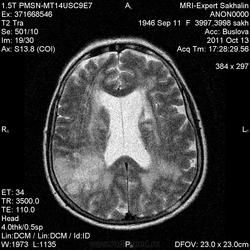

Ишемический инфаркт

Вот, Сергей Николаевич, я тоже указала, что НМК по ишемическому справа в СМА

ОНМК по ишемическому типу в бассейне правой СМА. Судя по очагам накопления в коре, подострое.

Последствия ОНМК с геморрагическим пропитыванием справа. Кистозно-атрофические изменения в левой гемисфере мозжечка (последствия ОНМК ). Множественные очаги сливного характера вещества головного мозга ( поля лейкоариоза)

Да хотела еще добавить возможно у пациента еще были лакунарные инсульты. В области базальных ядер( слева ) определяются кисты, окруженные глиозом. И на предпоследнем изображение в правой гемисфере мозжечка по- моему и также есть нмк.

Гглиоз, сосудистые очаги, лейкоареоз - это все при ДЭП, этим и обусловлена деменция.